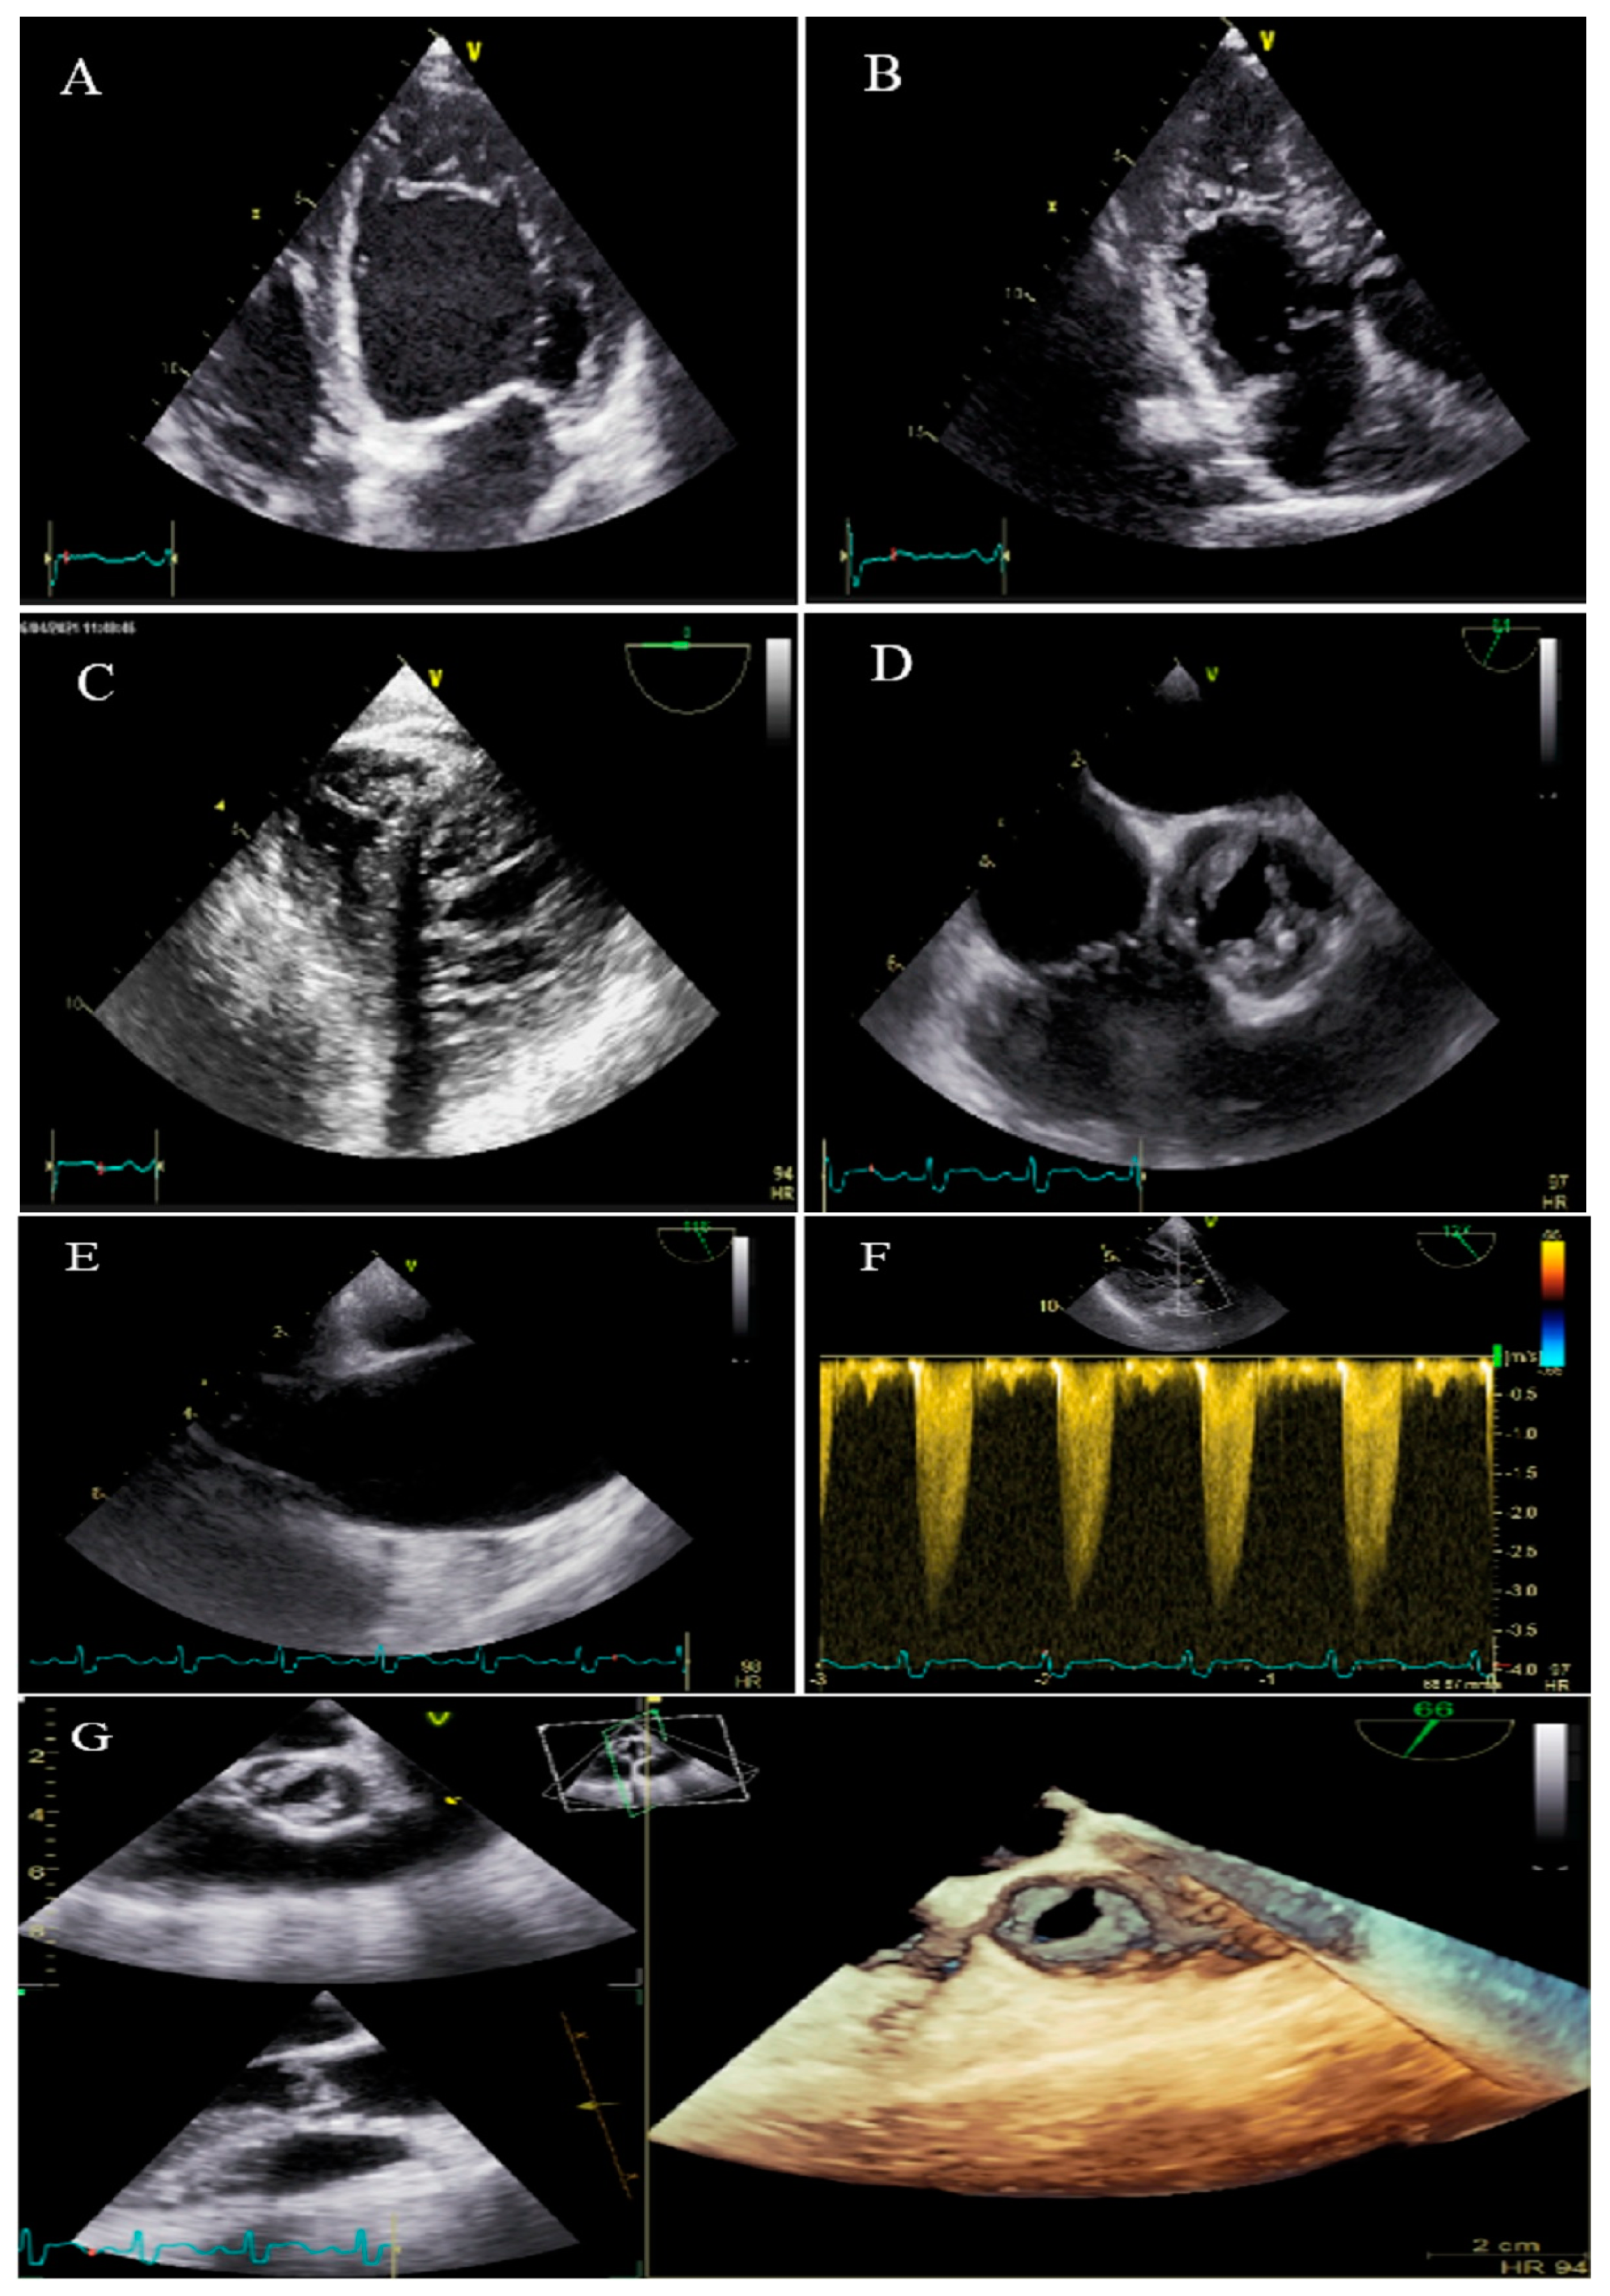

2.7. Case #7. BVNC, BAV, AS, and Dilated Aorta Ascending Aorta